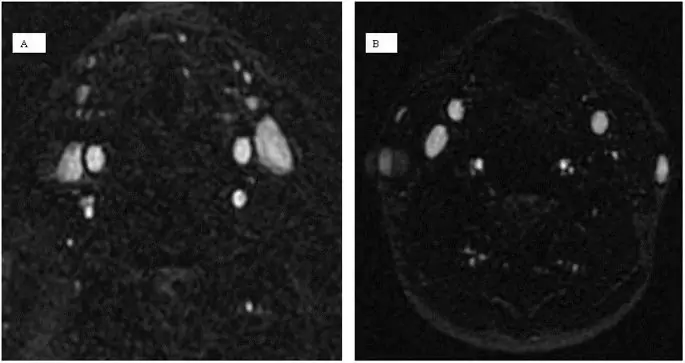

Аксиальная ориентация захвата обеспечивает высокое плоскостное разрешение, которое идеально подходит для измерений площади поперечного сечения (CSA) вен. Однако на последовательность TOF легко влияют артефакты движения, особенно от дыхания, глотания, храпа или движения головы пациента (38, 41) (рис. 4). Относительная нечувствительность к потоку в плоскости - еще одно ограничение метода TOF. Что касается направления потока, оптимальная плоскость сбора данных является ортогональной, что неэффективно с точки зрения времени получения и не всегда достижимо. Хотя он имеет более высокое пространственное разрешение, 2D-TOF может переоценивать стеноз в условиях турбулентного или медленного потока (42).

figure4

Пример нормального и аномального кровотока во внутренней яремной вене при магнитно-резонансной венографии. Нормальный кровоток в обеих внутренних яремных венах (A) и ненормальный кровоток в левой внутренней яремной вене на осевом 2D времени пролета (B).